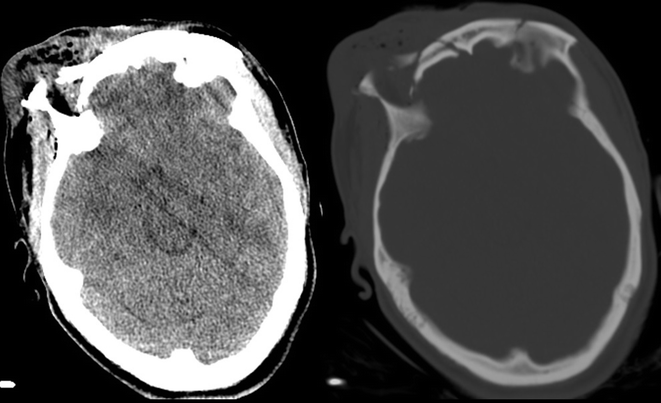

Fig. 19.9

Noncontrasted CT of head demonstrating comminuted fracture of the orbital bandeau and orbital roof and extra-cranial soft tissue swelling

Fig. 19.10

Three-dimensional reconstruction showing complex cranial, facial, and orbital fractures

Fig. 19.11

Three-dimensional reconstruction showing complex cranial, facial and orbital fractures

A 30-year-old female ejected from a motor vehicle after an unrestrained, head-on collision sustained direct craniofacial depression from a highway shoulder rail. On arrival, she was GCS 8T (E2-M5-V1T) and moving extremities symmetrically. She had gross brain matter and mixed serosanguinous fluid draining from an open facial laceration that extended from the middle of her forehead through her upper lip.